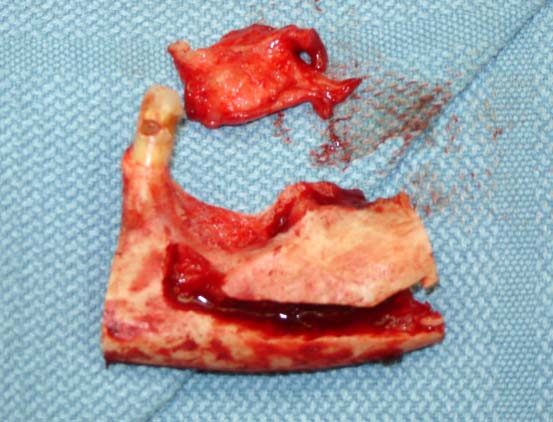

Head and Neck Tumor and Reconstruction

(cancer reconstruction)

Often after a patient has gone through various treatments for cancer there is a need that oral and maxillofacial services can provide for. In many cases, reconstructive surgery benefits patients having gone through specific skin cancers that are typically found in and around the head and neck regions. Depending on the severity and location of the cancer, skin cancer reconstruction options can range from simple to advanced procedures in order to restore both function and form.

The photos on this website are from real surgeries performed by Dr. Ulloa. Due to the

graphic nature of the images and content, viewer discretion is advised.